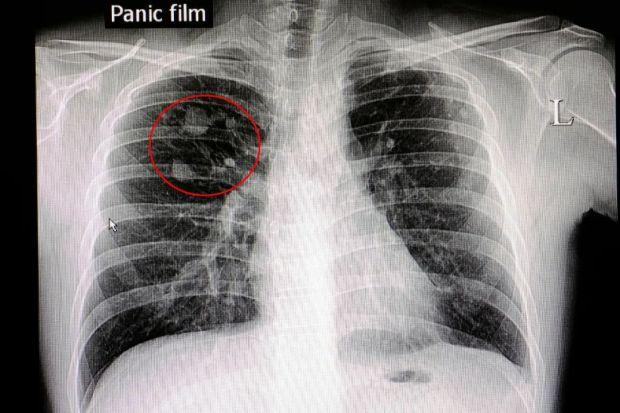

②肺结节

临床观察发现,经CT筛查发现的肺结节,绝大多数都是良性。

而肺结节是否有恶变的可能,可以根据以下3点来初步判断:

看“颜值”:良性结节多边缘光滑、密度均匀,属于“高颜值”;恶性结节则多半边界不光滑,密度不均匀,有毛刺、分叶、空泡、血管气管影等恶性征象。

看“家世”:有无肺癌等恶性肿瘤家族史,直系亲属有得过的话,要考虑遗传因素。

看成长轨迹:动态观察小结节的发展情况,有无增大,有无出现实性成分,或实性成分增加,密度增大等。

是否要手术切除肺结节,需要交给专业的胸外科医生判断。